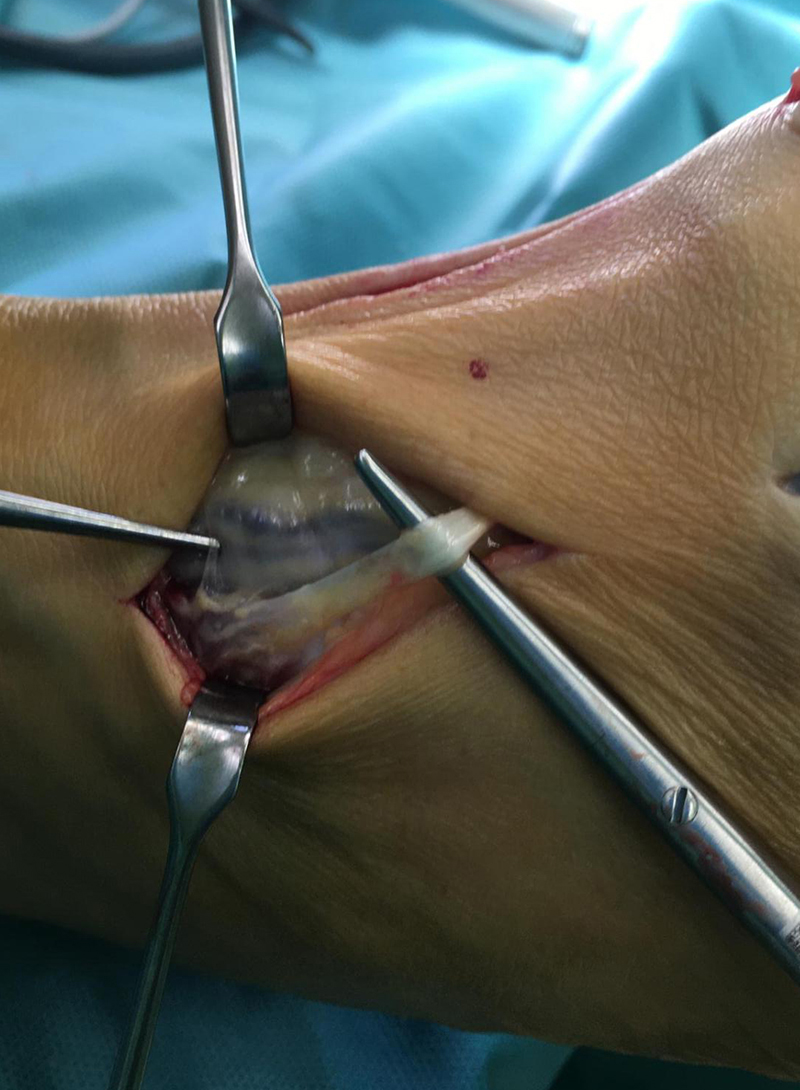

• In der Tiefe Schutz des Gefäß-Nervenbündels mit A. dorsalis pedis und N. peronaeus profundus. Meist ist es einfacher das Gefäß-Nerven-Bündel nach medial zur retrahieren (Abb. 15).

• Identifizieren und weghalten der Sehne des M. extensor hallucis brevis (Abb. 16 + 17).

• Eröffnen der Gelenkkapsel (Abb. 18).